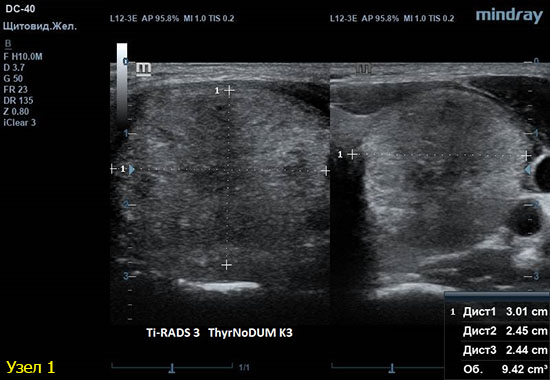

1) Узел занимает всю левую долю, но прорастает капсулу щитовидной железы (0 баллов), больше широкий чем высокий (0 баллов), не имеет кальцинатов (0 баллов), с ровным четким контуром (0 баллов), изоэхогенный (1 балл), тканевой структуры (2 балла). Количество баллов 3, ACRTi-RADS 3, ThyrNoDUMК3. Показана пункция в связи с большим диаметром узла (более 2,5см для Ti-RADS 3)